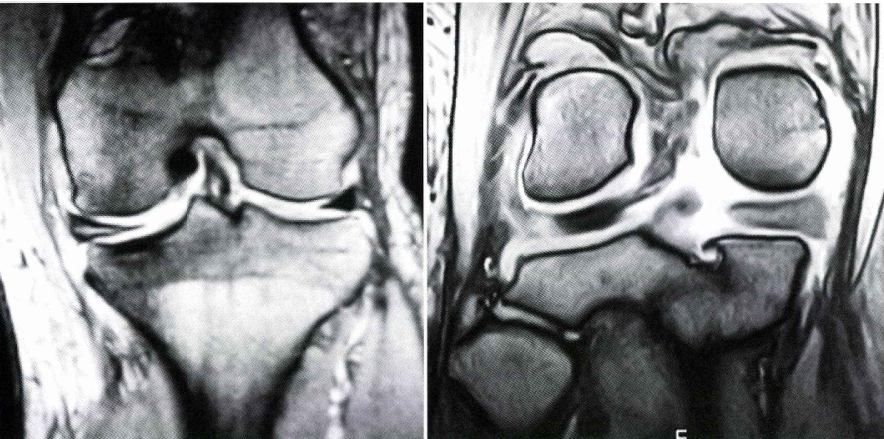

半月板損傷の診断

膝の痛み、圧痛の場所、可動域、水が溜まっているかどうかを診察で確認します。またマックマーレーテストと言い膝をねじることで痛みを誘発する診察法も行うことがあります。レントゲンを行い、膝の関節の隙間があるかどうか、変形性があるかどうかもチェックします。半月板損傷を疑う場合はMRIを行うことで半月板損傷の確定診断を行います。

半月板損傷の治療

まずは炎症を抑えることが重要です。そのためには炎症を抑える薬、湿布、塗り薬、サポーターなどで治療します。並行してリハビリをや物理療法を行い、総合的に治療していきます。当院では導入検討中ですが、PRPという再生医療の注射を行い、半月板の修復を促す治療があります。導入次第患者さまにお知らせさせていただきます。

保存治療で痛みが改善しない場合は、手術ができる病院へ紹介することがあります。